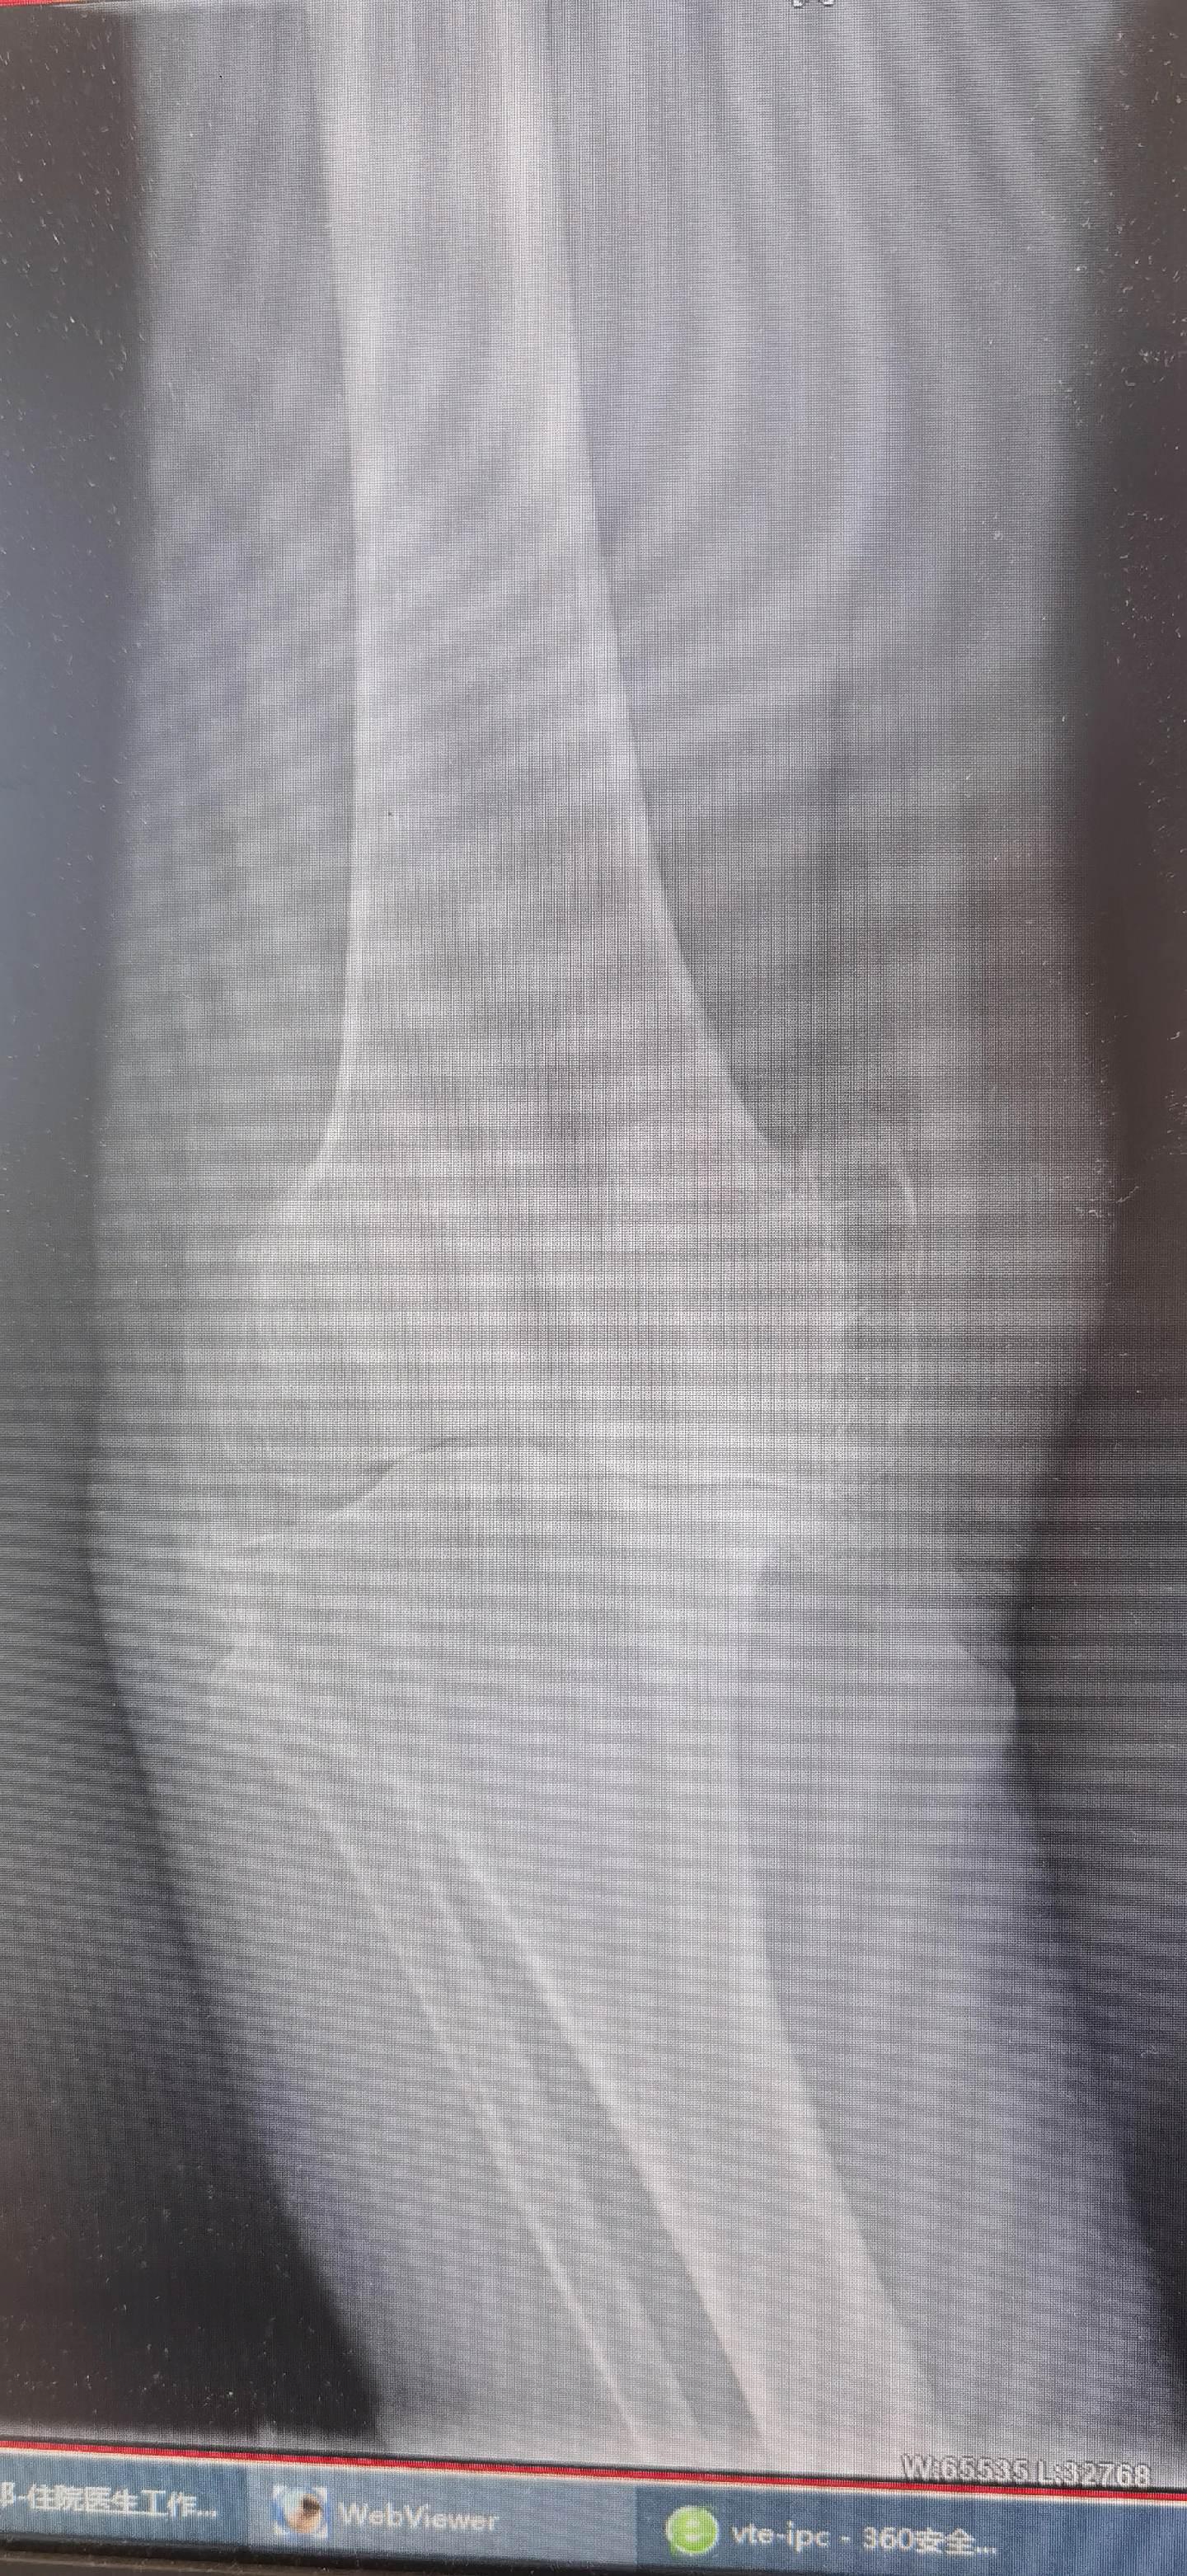

膝关节置换TKA.骨关节炎重度内翻合并屈曲挛缩畸形,无法行走,一期行双侧TKA,愿每一位患者都能得到有效的治疗,都能早日恢复正常生活🌹